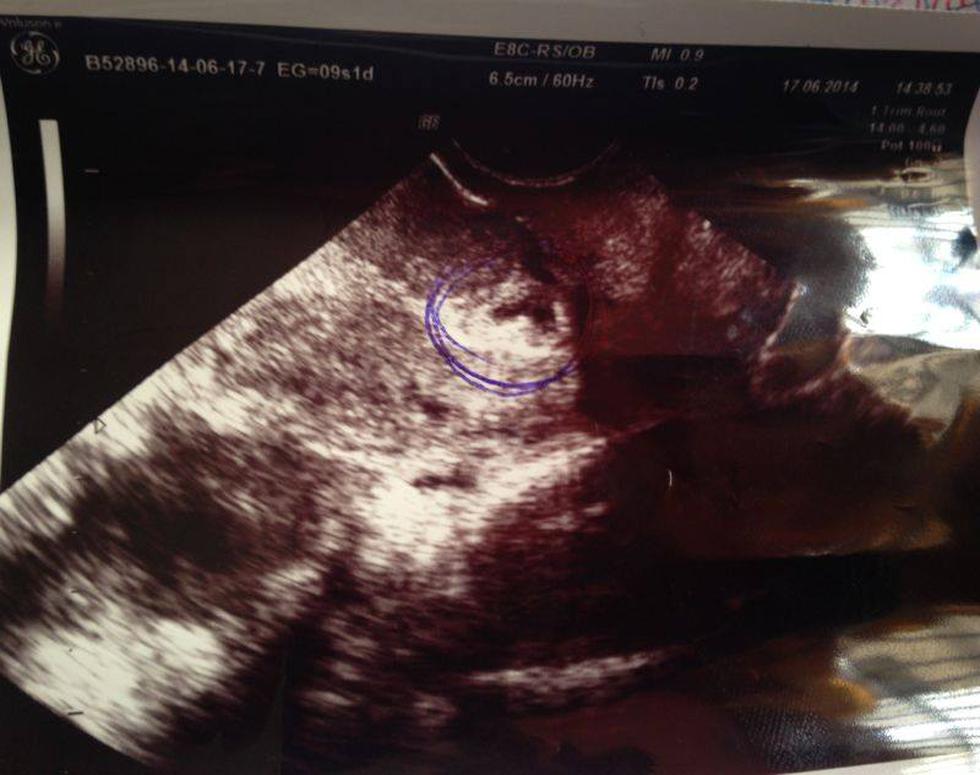

A través de la red social de Facebook, la cantante anunció que está embarazada y adjuntó una imagen de la ecografía del bebé que espera.